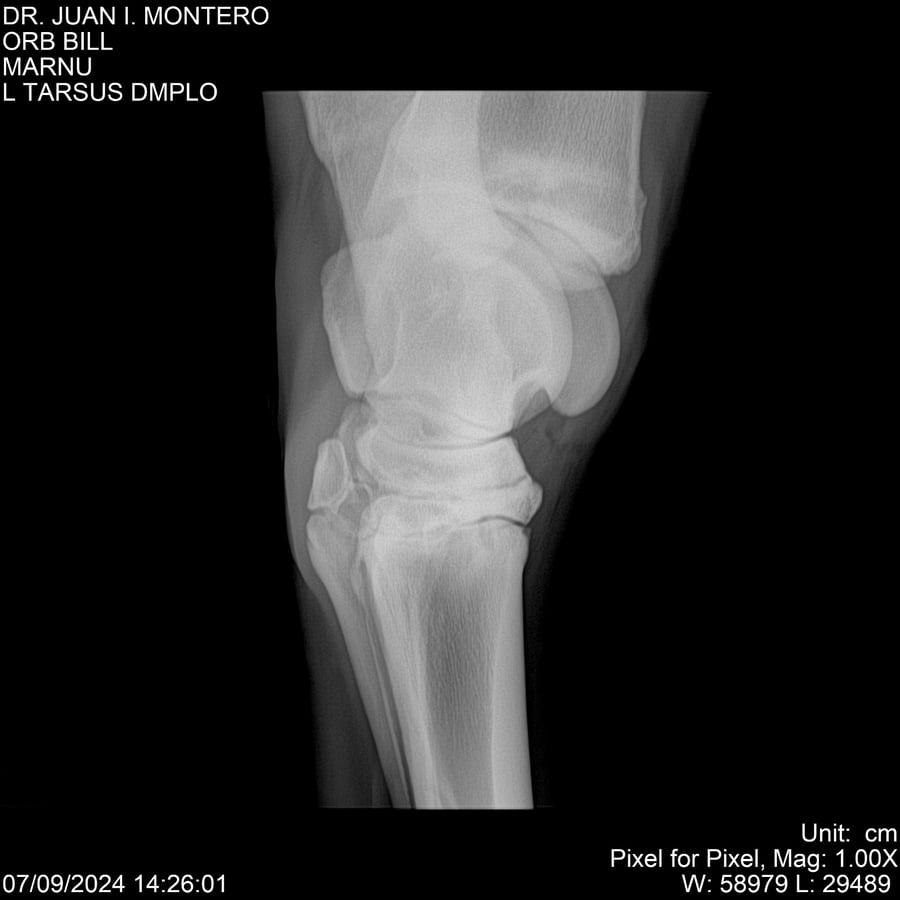

LOTE 7, ORB BILL 🔥 🔥 🔥 Lote Anterior Volver al remate Lote Siguiente Ficha Contacto Montevideo - Ficha del Lote Identificador: #282523 Categoría: Yeguarizos Montevideo - 83 Visualizaciones ClicData Contacto Empresa: Abelenda N. R., Walter Hugo Nombre*: Teléfono* : E-mail* : Mensaje Enviar Registrese gratis Este contenido Exclusivo está disponible sólo para usuarios registrados Ingresar